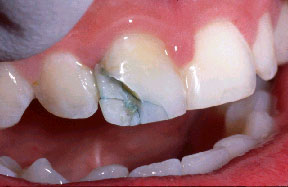

La queja principal de este paciente era la incomodidad durante el funcionamiento de los dientes anteriores inferiores. Nótese la pérdida y recesión de encía. Todos los incisivos tenían grado 2 de movilidad.

Otro factor que complicaba el caso fue que el paciente había completado dos años de tratamiento de ortodoncia para cerrar el espacio que existía en anteriores debido a la pérdida de un incisivo central por enfermedad periodontal. Hay evidencia radiográfica de pérdida de masa ósea de más del 70% en el incisivo central restante.